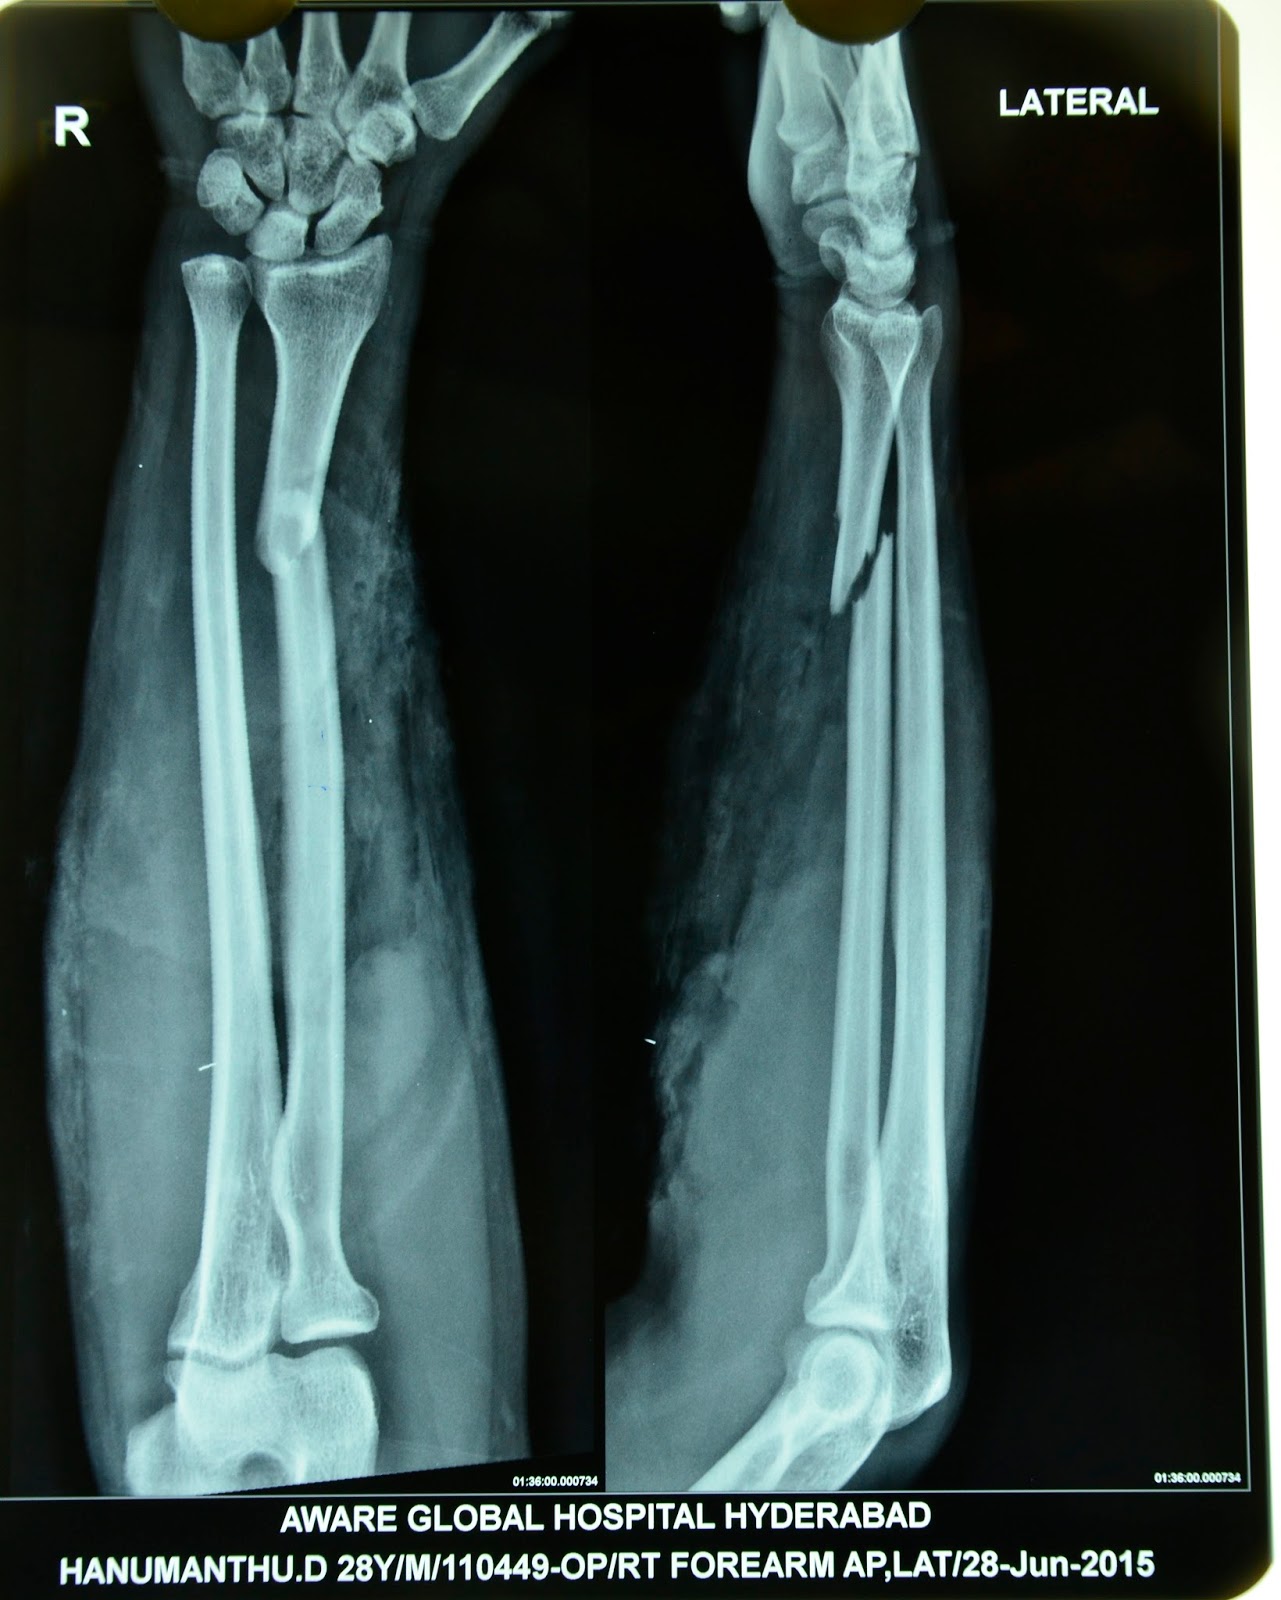

CRUSH INJURIES OF HAND AND UPPER LIMB INJURIES OPEN FRACTURE BOTH BONE FOREARM, GROSS Crush Injury Upper Arm It may result in asphyxia, severe orthopedic injury, compartment syndrome, hypotension, and organ injury (including acute kidney injury). This type of injury most often happens when part of the body is squeezed. Severe crush injury increases the risk for organ failure and death due to the possible development of crush syndrome, which is the. Injury caused as a result of. Crush Injury Upper Arm.